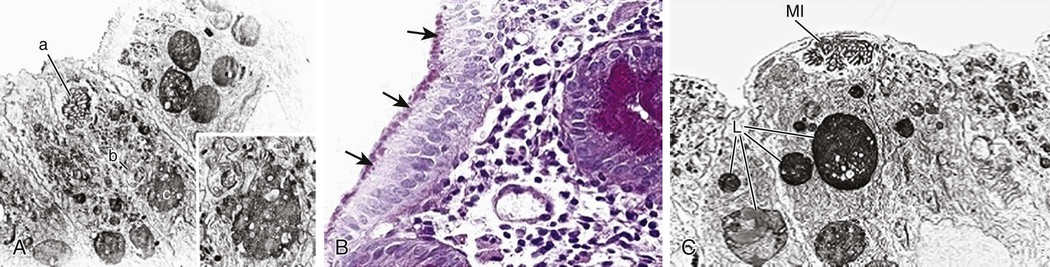

Structural enterocyte defects are caused by specific molecular defects responsible for early onset, severe diarrhea. In microvillus inclusion disease, microvilli are sequestered in vacuoles as a consequence of autophagocytosis because of a defect in protein trafficking disrupting enterocyte polarity (Fig. 341-2). Intestinal epithelial dysplasia (or tufting enteropathy) is caused by focal crowding of enterocytes that produce epithelial abnormalities resembling tufts (tears). Abnormal deposition of laminin and heparan sulfate proteoglycan on the basement membrane has been detected in intestinal epithelia. An abnormal intestinal distribution of α2β1 and α6β4 integrins is implicated in tufting enteropathy. These ubiquitous proteins are involved in cell–cell and cell–matrix interactions, and play a crucial role in cell development and differentiation.

Noninvasive assessment of digestive-absorptive function and of intestinal inflammation plays a key role in the diagnostic work-up (Table 341-5). Abnormalities in the digestive–absorptive function tests suggest small bowel involvement, whereas intestinal inflammation, as demonstrated by increased fecal calprotectin or lactoferrin, supports colitis. Histology is important in establishing mucosal involvement, noting changes in the epithelial cells, or in identifying specific intracellular inclusion bodies caused by pathogens, such as cytomegalovirus, or the presence of parasites. Electron microscopy is essential to detect subcellular structural abnormalities such as microvillous inclusion disease. Immunohistochemistry allows the study of mucosal immunity as well as of other cell types (smooth muscle cells and enteric neuronal cells).